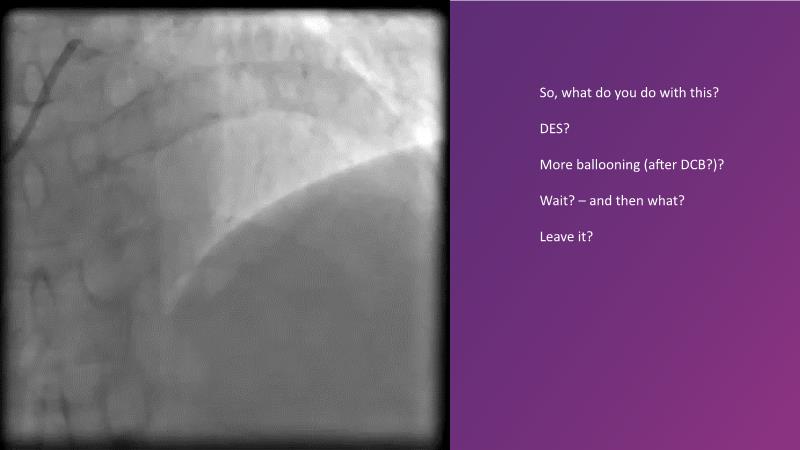

DES and DCB, can these two technologies be complementary for the treatment of the same patient? What are the advantages and how to proceed? You will know everything by watching this presentation based on concrete cases.

- To discuss cases when DCB and DES are complementary